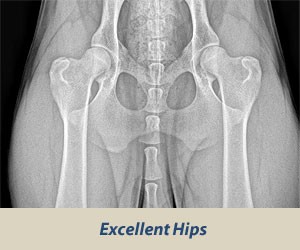

Excellent

Excellent: this classification is assigned for superior conformation in comparison to other animals of the same age and breed. There is a deep seated ball (femoral head) which fits tightly into a well-formed socket (acetabulum) with minimal joint space. There is almost complete coverage of the socket over the ball

.